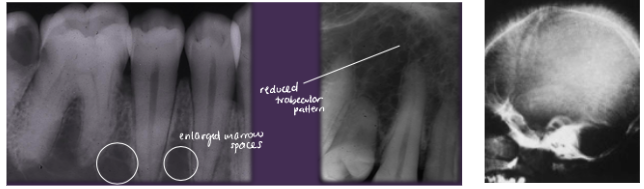

ORAL:

*Reduced trabecular pattern

*Enlarged marrow spaces

*“Hair-on-end” on skull x-ray

*Increased prevalence of osteomyelitis

*Spontaneous, asymptomatic pulpal necrosis

beta-thalassemia clinical features

Thalassemia Major

*Manifestations at ~1 yr

*Hemolytic anemia

*Increased hematopoiesis with bone marrow hyperplasia

and enlarged marrow spaces

*”Hair-on-end” appearance on skull xray

*Enlargement of liver & spleen, lymphadenopathy

*Enlargement of maxilla and mandible (“chipmunk faces”)

*Altered trabecular pattern